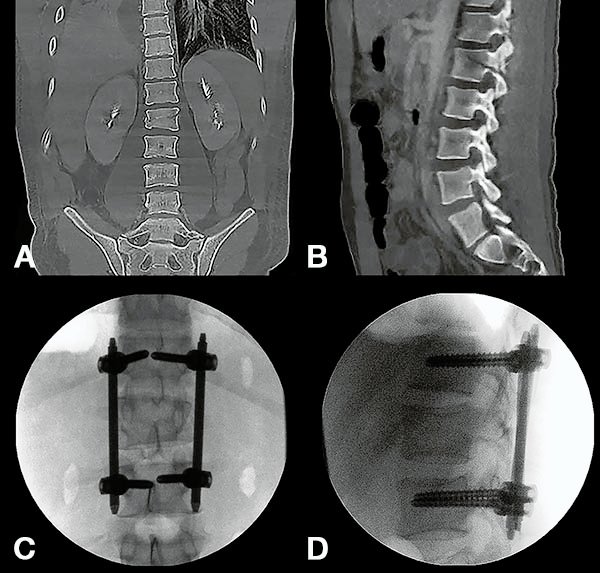

Figura 2:

Caso 24. A y B: Fractura horizontal que compromete cuerpo, pedículo izquierdo y apófisis espinosa de L1 (L1: B1; N1 AOSpine). C y D: Estabilización percutánea T12-L2.